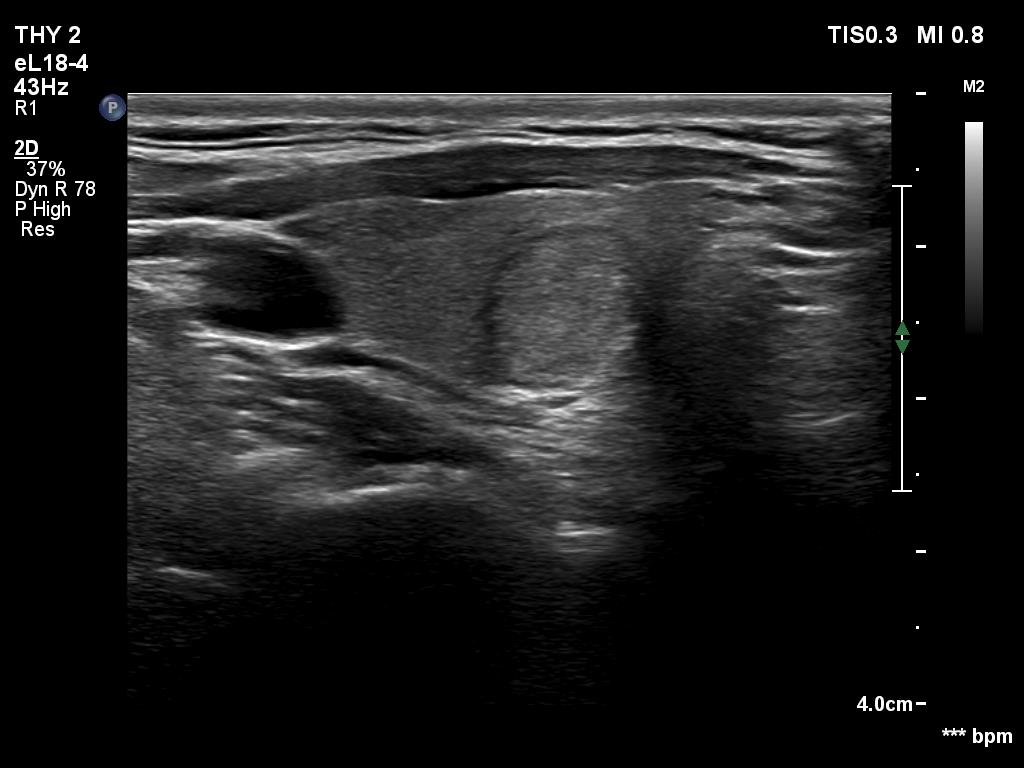

Ultrasonography. The thyroid was echonormal or minimally hypoechogenic. There was an iso/hyperechoic nodule in the right lobe. The lesion had halo and sowed taller-than-wide shape. The vascularity was not specific.

Comments. The nodule is an EU-TIRADS 5 lesion due to the nonparallel orientation.